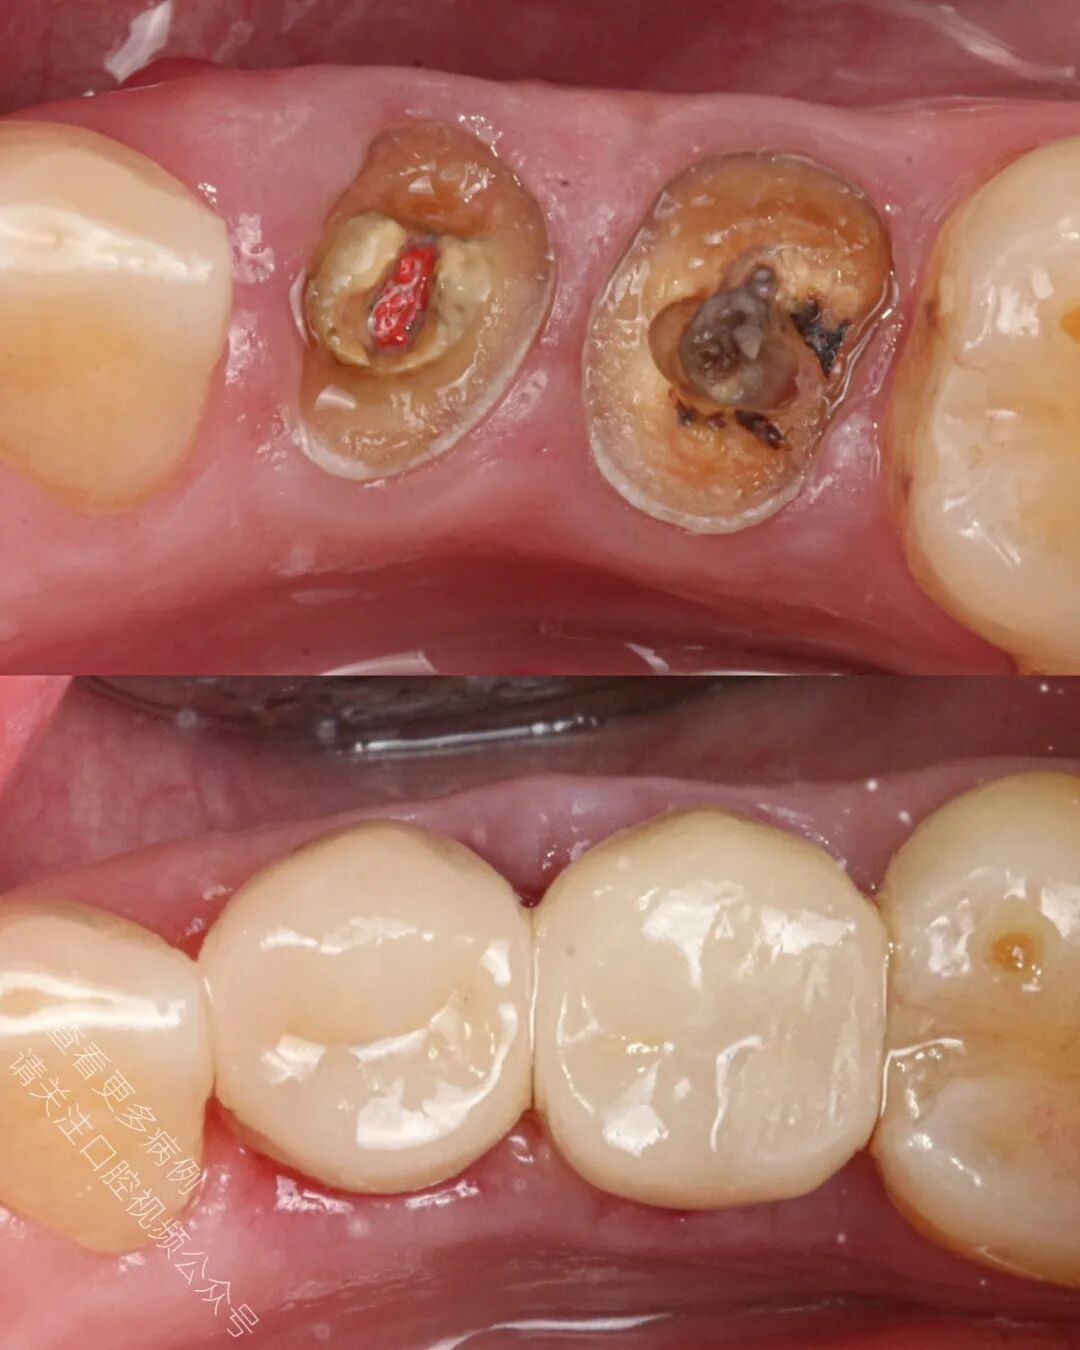

从深龋坏到完成全冠修复——给这些牙齿最后一次重生的机会。

🪄 成功使用橡皮障隔离,对两颗前磨牙进行了再根管治疗(ReRCT)

🪄 使用纤维桩进行核修复(也可选择嵌体冠 endocrown 作为替代方案)

🪄 冠修复体制作完成后返回诊所,在隔离环境下完成粘接